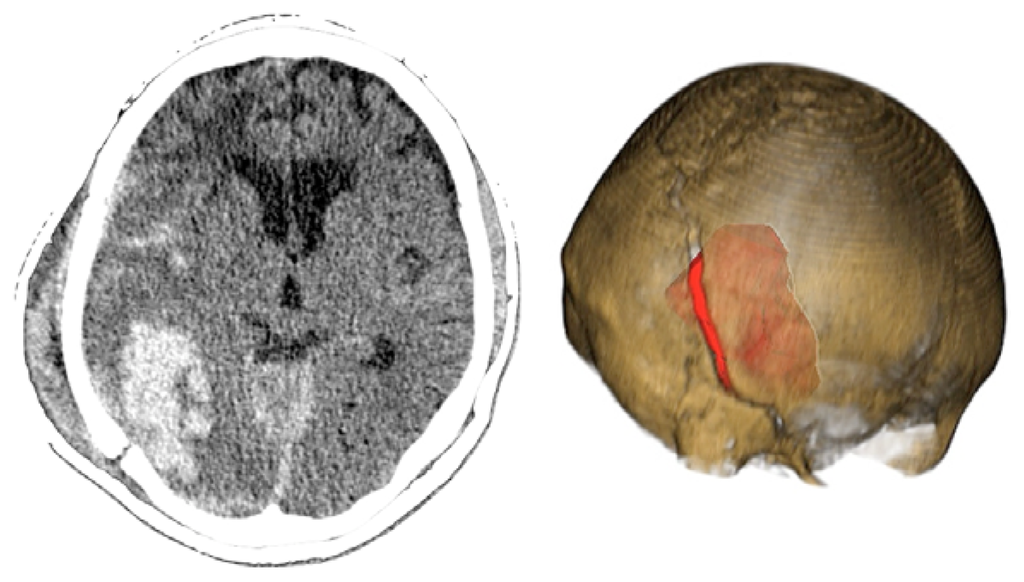

Case 3-Contusional Hematomas (See Figures 5 and 6 for the details)

A 61-year-old alcoholic man was a patient who was hit by a motorcycle. Initially, he was alert and fully oriented. In the emergency department, the patient became disoriented; the examination revealed no signs of injury, and coagulation studies were normal. Within 30 min after the initial evaluation, his neurologic status deteriorated (GCS of 8). The CT scan revealed an acute right-sided post-traumatic intracranial parietal contusion containing an intraparenchymal hematoma, and acute subarachnoid hemorrhage in the right sylvian fissure. The patient underwent intubation and referred promptly to the operating room. Through the interpretation of the images 3D, we identify the best entry point for an endoscopic approach through a burr-hole. The patient had adequate recovery and was discharged seven days after surgery.